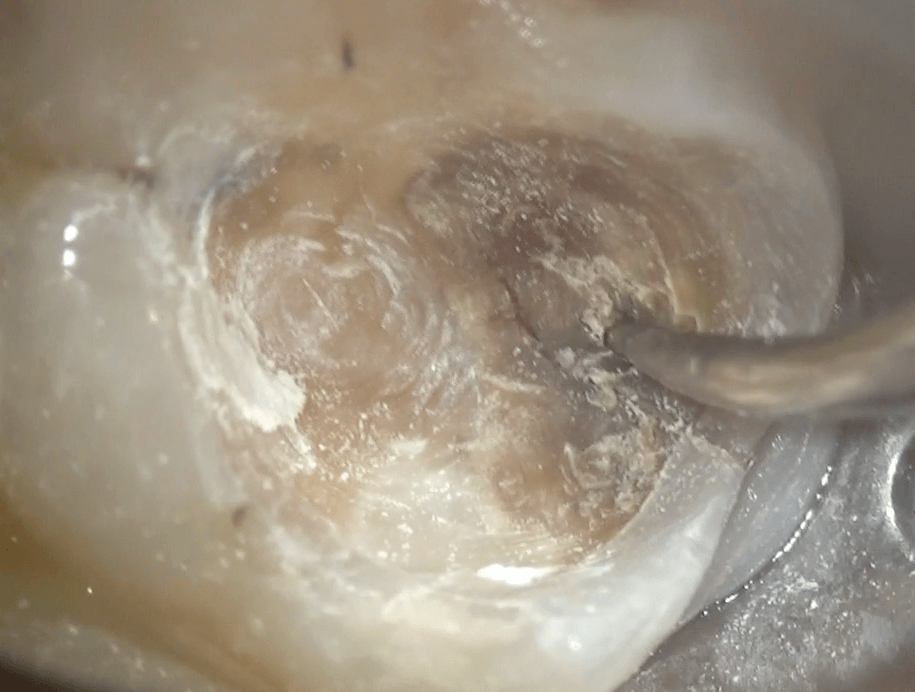

実際の治療を提示致します。麻酔をして、つめものを取り除き、内部をみると、柔らかく、

ボソボソしています。これが虫歯です。